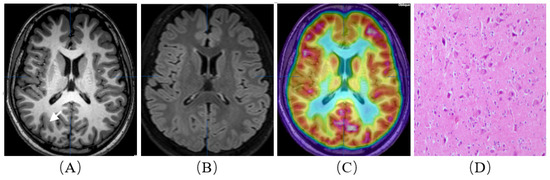

Figure 1.

A patient with refractory epilepsy to drug therapy. She was born in 1993 and was admitted when she was 26 years old. Her first seizure occurred at 16 years old. Neither MRI nor (18F)-FDG PET/MRI (A–C) showed the epileptic focus. Resective surgery was planned for the patient, and an intracranial electrode was used. The intracranial electrode indicated the right frontal lobe region. Postoperative histopathological examination confirmed ‘type Ⅰ b, focal cortical dysplasia’ (D). The patient is currently seizure-free (Engel III–IV).